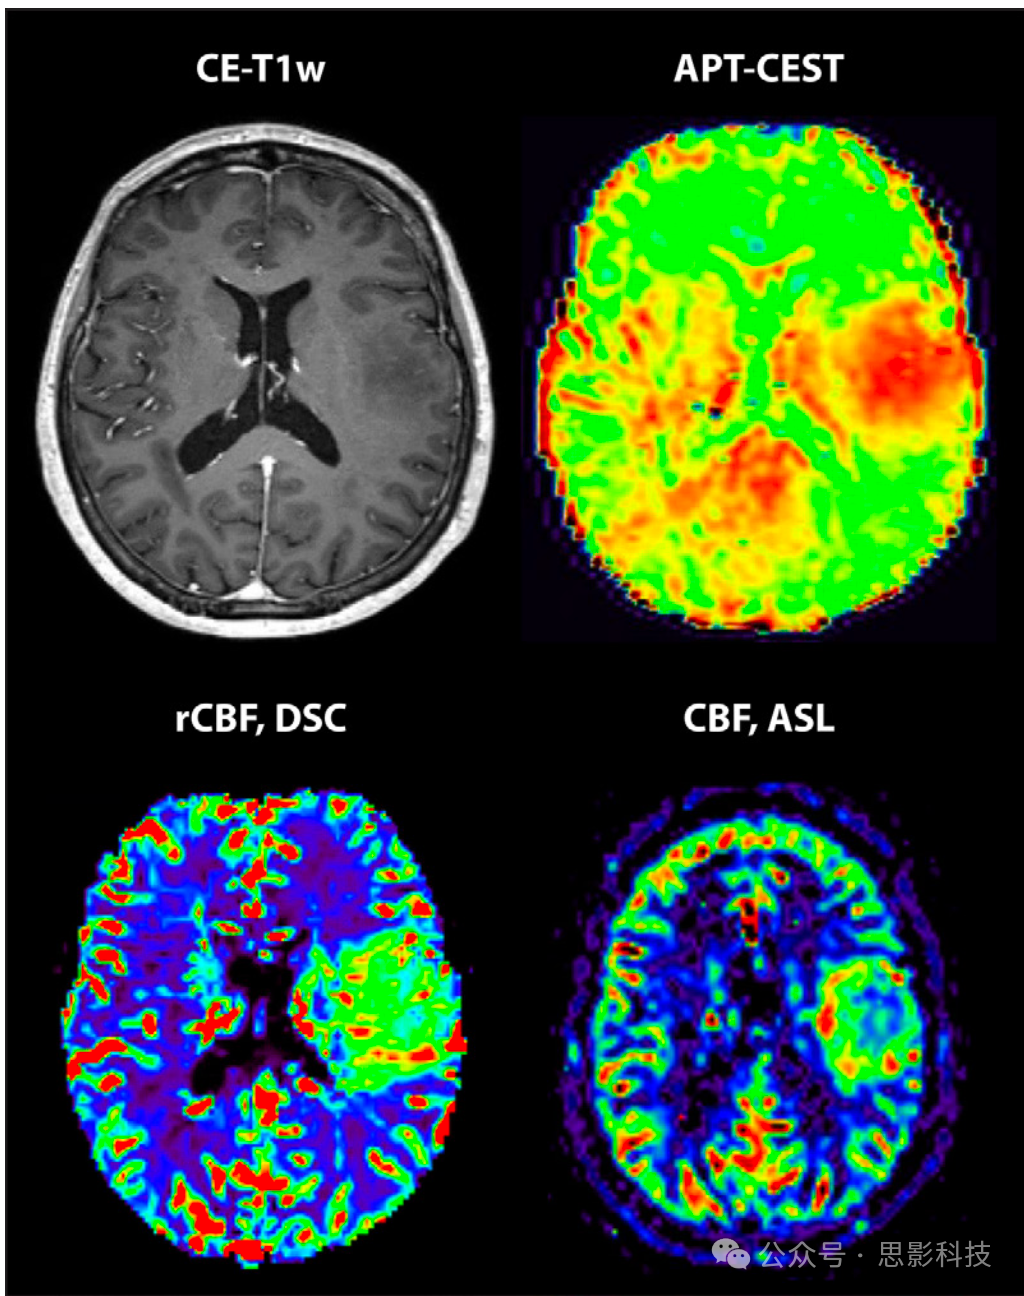

动脉自旋标记——动脉自旋标记(ASL)通过测量脑血流量(CBF)无创地描绘肿瘤血管化(图4),有可能取代DSC成像。研究表明,ASL和DSC成像在区分HGG(高级别胶质瘤)和LGG(低级别胶质瘤)方面具有同样高的性能(AUC均为0.9;ASL相对CBF cut-off值为1.36;n=44)(36)。与DSC成像一样,当将肿瘤CBF标准化到对侧正常灰质时,ASL可获得更可靠的结果,以减少CBF的测量和生理变异性。然而,最佳cut-off值因扫描仪和ASL实现的不同而异,需要进行多中心验证研究。另一种无创肿瘤血管化评估方法是通过弥散加权成像的体素内非相干运动模型测量毛细血管微循环。一项研究(n=30)表明,它是异柠檬酸脱氢酶状态的更好预测因子(AUC为0.81),优于动态CE成像衍生参数Ktrans(AUC为0.773)(37)。

图4:一例非增强性左额岛胶质母细胞瘤(异柠檬酸脱氢酶野生型)的对比增强T1加权(CE-T1w)、酰胺质子转移化学交换饱和转移(APT-CEST)、动态磁敏感对比(DSC)和动脉自旋标记(ASL)图像。在肿瘤位置,即使在T1低信号区域之外,酰胺含量也有所增加(APT-CEST扫描上为红色)。DSC相对脑血流量(rCBF)图和ASL脑血流量(CBF)图之间具有良好的一致性,均显示病变处有高灌注(病变位置为绿色和红色),是恶性肿瘤的标志。

比较GBCA和无GBCA方法在儿科人群中的研究很少。然而,一项研究(n=37)发现,ASL在区分高级别和低级别星形细胞瘤方面达到了与DSC成像相似的性能(cut-off值为0.82时,敏感性为100%,特异性为95.5%)(38)。

ASL也是DSC成像治疗监测的一种潜在无创替代方法。在区分胶质瘤复发和放射效应方面,ASL与DSC性能相当,CBF较低(n=69;ASL:cut-off值1.86,准确率79.7%;DSC准确率82.6%)(39),可区分复发和假性进展(n=116;ASL AUC 0.72;DSC AUC 0.87)(40)。ASL还可能有助于在较低磁场强度(即1.5T)下识别假性进展(n=26;ASL准确率69%;MR波谱准确率74%;动态CE MRI准确率69%;DSC准确率79%)(41)。

分子成像:酰胺质子转移化学交换饱和转移和MR波谱——研究最多的肿瘤分子特性成像方法之一是酰胺质子转移化学交换饱和转移(APT-CEST)(图4),这是一种对含有可交换质子的蛋白质和肽敏感的新序列。使用APT-CEST的研究远少于ASL。初步结果表明,APT-CEST(AUC 0.911)在识别假性进展方面可能优于ASL(AUC 0.852)(n=48)(42)。APT-CEST(cut-off值1.53;AUC 0.877)和DSC(AUC 0.927)不仅在胶质瘤患者(n=46)中对HGG和LGG进行分类的表现相当好(43),而且APT-CEST(cut-off值2.56;AUC 0.886)能够帮助在无明显对比增强的胶质瘤中对肿瘤进行分级(n=34)(44)。